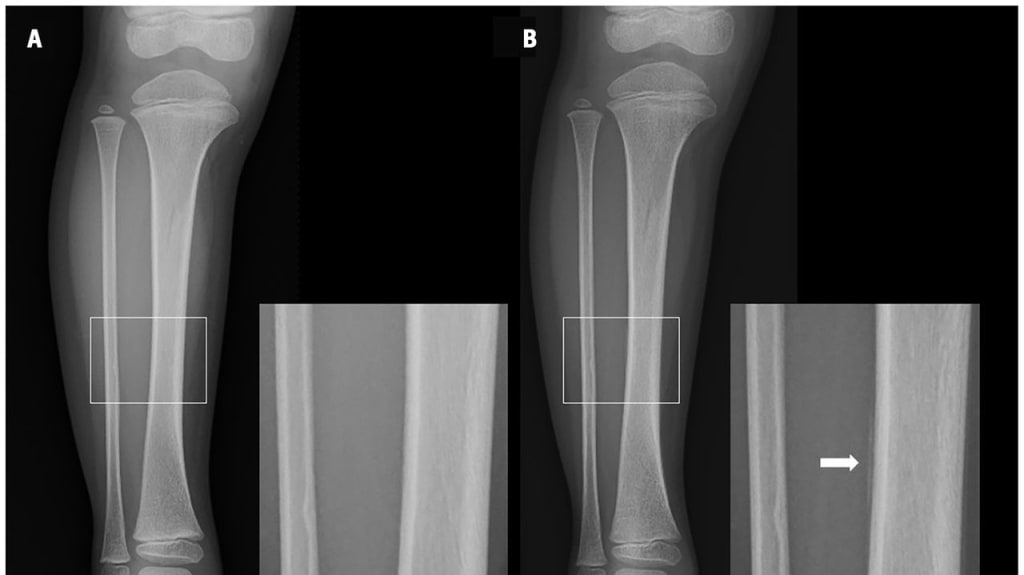

Ein 3-jähriges Mädchen wurde mit Hinken in die Notaufnahme gebracht. Am Morgen der Vorstellung war sie von einer Treppenstufe gesprungen und weigerte sich anschließend, aufzustehen.

Abb.1 Röntgenaufnahmen des rechten Unterschenkels eines 3-jährigen Mädchens, aufgenommen (A) am Tag der Verletzung und (B) 11 Tage nach der Verletzung. Vergrößerte Bilder des mittleren Schienbeinbereichs sind für beide Aufnahmen enthalten.

© Iio K & Kimura Y. CMAJ 2025; 197 (39): E1314-E1315